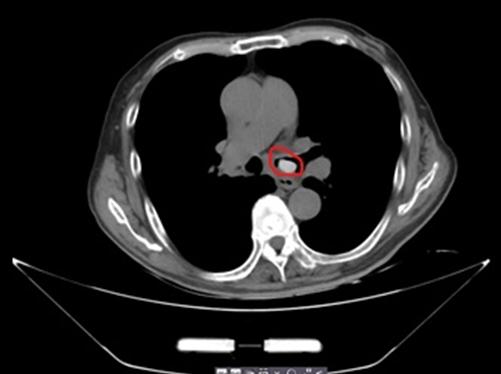

果然,胸部CT提示“左侧主支气管异物”,可不就是那颗硕大的琵琶核!几乎把左侧支气管都给堵住了。

李惠利东部医院呼吸内科主任汤耀东当机立断,为胡大爷进行了局麻下施行“”支气管镜检查+取异物术“”。支气管镜下可见左主支气管远端大小约1.5cm*1.0cm大小的异物,因为枇杷核外表十分的光滑,加之粘液的覆盖,气管镜下抓取有一定困难。好在医生娴熟的支气管镜操作技术很快将琵琶核取出。胡大爷立即感呼吸畅快了。